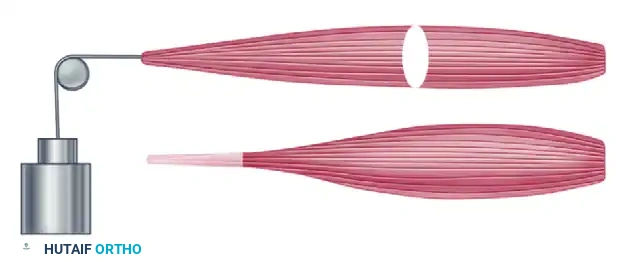

Setting the correct tension is the most technically demanding aspect of any tendon transfer. If the FPL is sutured too loosely, the transfer will fail to abduct the thumb dynamically. If sutured too tightly, it may create a fixed abduction deformity, preventing the thumb from opposing the digits for pinch. The Blix curve dictates that the muscle must be tensioned at its optimal resting length.